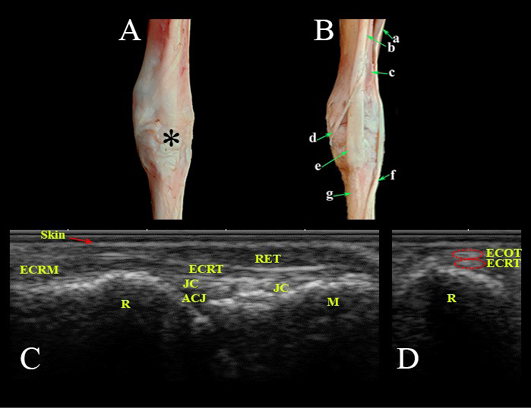

Dorsal aspect of the carpal region. Photomacrographs: (A) superficial layer and (B) deep layer. Ultrasonographic imaging: (C) Longitudianl scan (LS) and (D) Transverse scan (TS) at the level of the radius. *- Extensor retinaculum; a- Common digital extensor M.; b- Extensor carpi radialis M.; c- Extensor carpi obliqus M.; d- Tendon of extensor carpi obliqus M.; e- Tendon of extensor carpi radialis; f- Tendon of common digital extensor M.; g- Metacarpal bones; Ret- Retinaculum; ECRT- Extensor carpi radialis tendon; ECRM- Extensor carpi radialis M.; ECOT- Extensor carpi obliqus tendon; JC- Joint capsule; ACJ- Antebrachiocarpal joint; R- Radius; M- Metacarpus.